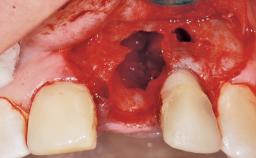

Immediate Flapless Placement of an Implant in a Maxillary Right Lateral Incisor Site

This 43-year-old male patient, a non-smoker, came to our practice because of a fracture of tooth 12 caused by a bicycle accident. Due to the combined para- and infrabony crown and root fracture, tooth extraction, and subsequent implant placement were suggested to the patient as the therapy of choice. The patient had high esthetic expectations with regard to the treatment outcome and asked for an immediate fixed provisional restoration. His individual esthetic risk profile summed up to a medium esthetic risk.

Socket Morphology Single-root socket

Socket Integrity Sufficient, with intact bone walls

Bone Volume Sufficient, with intact walls